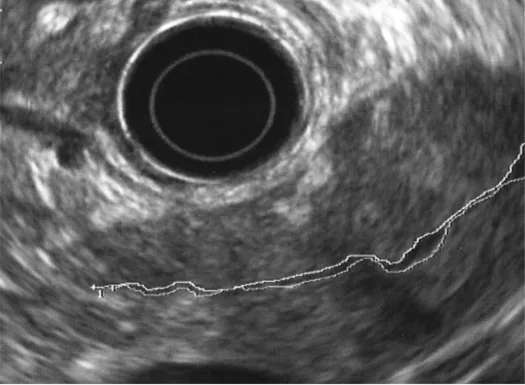

Quels sont les signes écho-­endoscopiques évocateurs de PAI ? (Figs 11- 14)

1) La ductite : c’est l’association d’un remaniement important du calibre du canal pancréatique principal (CPP), alternant des segments où il est sténosé (sténose longue) mais encore repérable, collabé, et des segments où il est normal voir dilaté (> 3 mm mais < 5 mm de diamètre), et d’un épaississement hyperéchogène ou hypoéchogène (comparé au parenchyme avoisinant) de sa paroi.

Point essentiel, cet aspect est retrouvé à la fois dans la forme diffuse (hypertrophiante classique ou atrophique plus rare) et dans la forme focale pseudo-tumorale, on parle alors de « penetrating sign » ce qui correspond à la mise en évidence du canal sténosé ou collabé, mais visible dans la pseudo tumeur, signe exceptionnellement retrouvé dans l’adénocarcinome pancréatique. Dans notre expérience, dans une étude cas/contrôle effectuée à l’hôpital Beaujon [21] comparant des PAI absolument certaines, des cancers du pancréas et des pancréatites chroniques classiques, la sensibilité et la spécificité de ce signe étaient très élevées (> 90 %). L’épaississement hyperéchogène de la paroi (Fig. 12) était plus souvent observé dans la PAI de type I, tandis que l’épaississement hypoéchogène (Fig. 13) était surtout observé dans la PAI de type II.

Figure 13. Aspect échoendoscopique de la PAI de type II. Noter l’épaississement hypoéchogène de la paroi du CPP responsable d’un aspect filiforme de la lumière du CPP